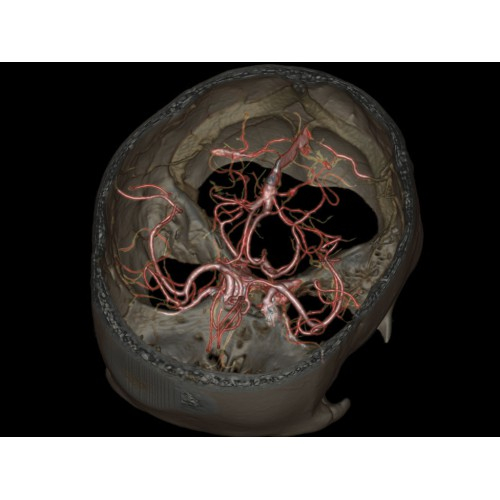

Позволяет проводить комплексные исследования всех анатомических зон, включая нейровизуализацию, ангиографию, исследования органов грудной и брюшной полости. Особенно эффективен для раннего выявления онкологических заболеваний.

Обеспечивает высокую точность при кардиологических исследованиях, визуализации костных структур и суставов. Подходит для динамического наблюдения в ходе лечения.